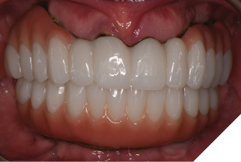

The patient returned 2 months later (due to patient scheduling delays) and the maxillary and mandibular Nexus restorations were inserted (Figs. 26A-C). Passive seating of the restorations were confirmed with the Sheffield test and radiographic confirmation. The occlusion was checked and final radiographs taken (Fig. 27).

Fig. 26A

Fig. 26B

Fig. 26C